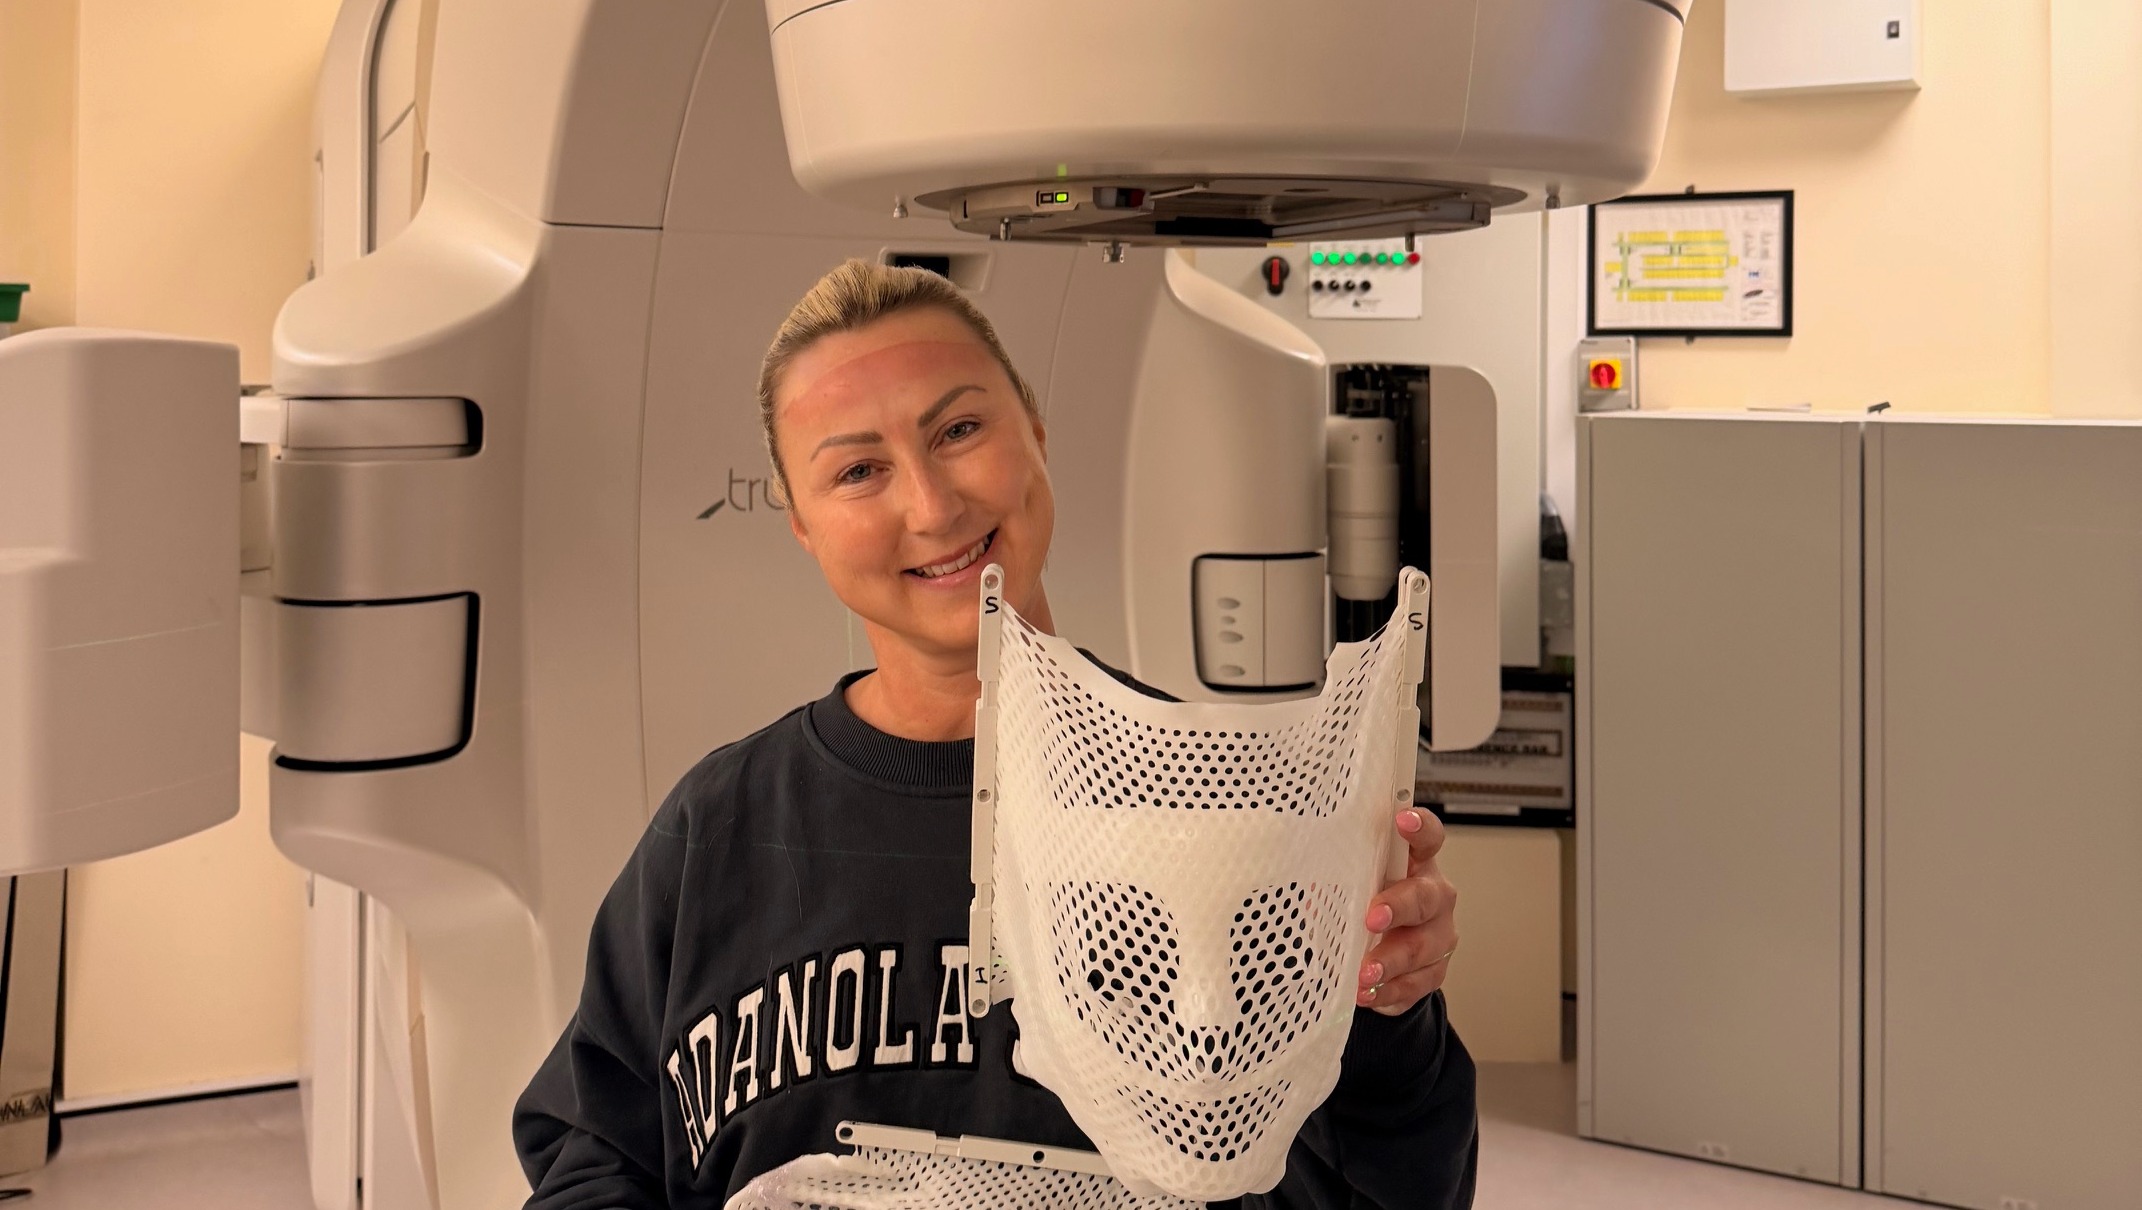

Katie undergoing intensive treatment to fight against cancer.

Mum fighting to be there for her boys